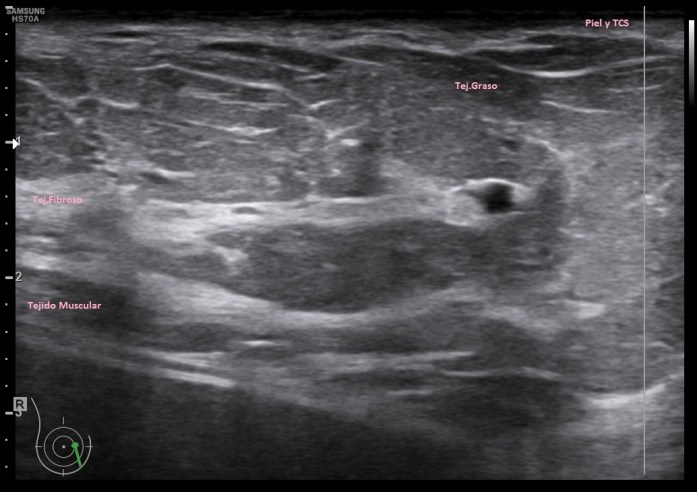

La clínica ya la conocemos, la semiología os la presento aquí. Ecográficamente la mastitis se ve como una zona donde el tejido varía la ecogenicidad, se vuelve más hiperecogénico, aumena su tamaño, incluso su vascularización. La piel se puede ver engrosada. El tejido mamario puede verse heterogéneo, simulando lesiones de otra índole, es decir, su aspecto puede ser variado.

Ecográficamente, encontraremos una zona afectada, de la manera descrita en el párrafo superior, y junto a ella, en una zona normal, sin afectación la semiología normal de la mama.

La imagen 1 y la imagen 2 son normalidad con anatomía básica y semilogía patológica respectivamente. Compara amabas imágenes para darte cuenta de como cambia el tejido afecto por la mastitis en este caso. No olvides que hay otras patología que pueden afectar el tejido modificando su ecoestructura normal de forma similar.